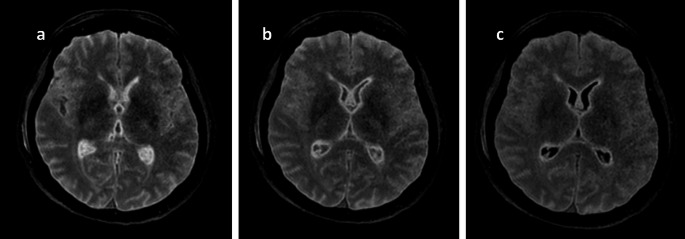

Introduction: Postmortem magnetic resonance imaging (PMMR) has gained importance during the last decade in forensic pathology. While many clinical radiology sequences are applicable for the evaluation of the brain, the 3D FLAIR sequence shows different contrast in postmortem cases compared to living patients. Two factors-the temperature and the interval between official declaration of the death and PMMR (DC-PMMR interval) are suspected to influence the optimal inversion time (TI) needed to achieve living patient-like image contrast. This study aimed to investigate if our empirical approach had the same results as previous study.

Materials and methods: 3D FLAIR sequences with varying TI values (from 1660 ms to 900 ms, every 110 ms) were acquired. Two radiologists independently assessed the images, selecting the TI that produced the most patient-like contrast. Rectal temperature and the DC-PMMR interval were recorded, and Pearson correlation tests were conducted to evaluate interrelations between TI, temperature, and DC-PMMR interval. Interobserver reliability was assessed using PABAK.

Result: Overall, 23 cases were analyzed. Rectal temperature ranged from 5.7 °C to 29.0 °C, and the DC-PMMR interval from 13.05 to 768 h. A moderate interobserver reliability (PABAK = 0.56) was observed. Significant correlations were observed between TI and both temperature (r = 0.70, p = 0.0014) and DC-PMMR interval (r = - 0.68, p < 0.0003).